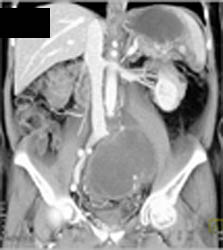

Coronary Artery Disease